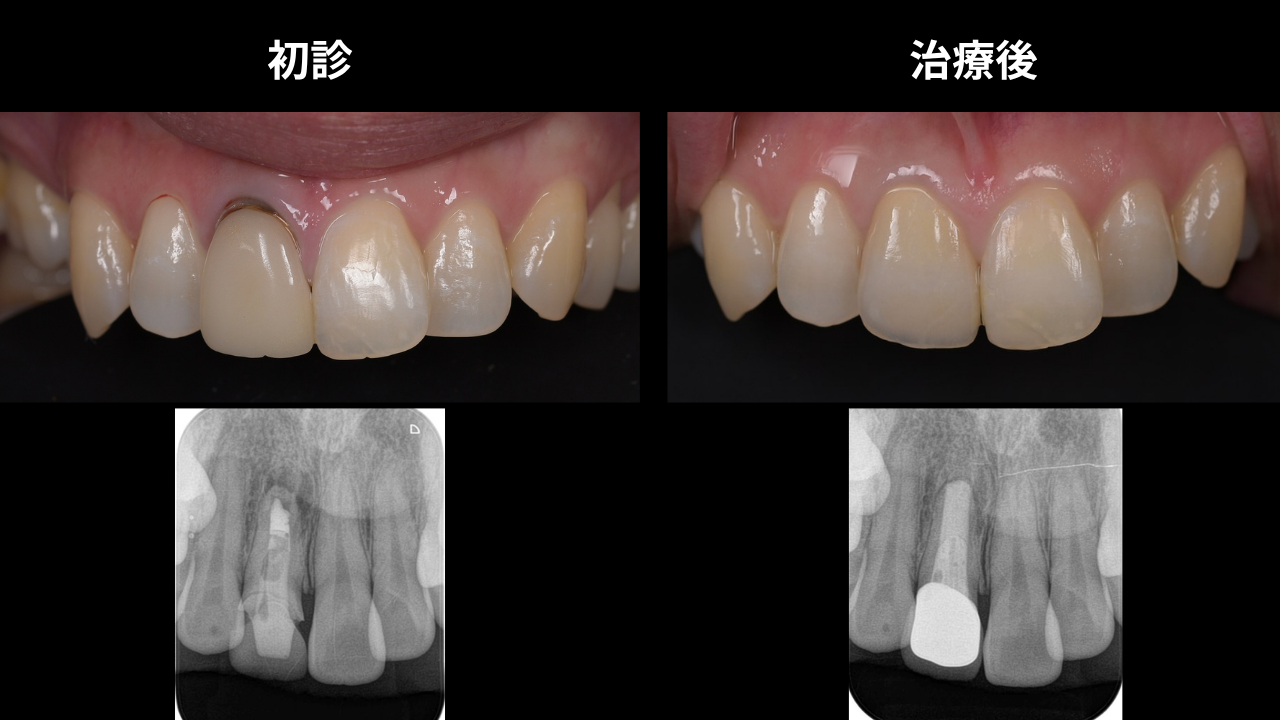

症例紹介|33歳女性・前歯の差し歯をやり直したい

来院のきっかけ

「以前に治療した前歯の差し歯が気になる。根元が黒くなってきたし、古くなってきたのでやり直したい」というご希望で来院された33歳の女性患者様です。

見た目の問題だけでなく、根の中の状態も確認が必要なケースでした。

治療前の状態

お口の中を確認すると、差し歯の根元に黒ずみがあり、歯茎との境目が目立つ状態でした。レントゲンを撮影すると、根の先端に細菌感染による病巣(黒い影)が確認されました。

上の被せ物(差し歯)だけを交換しても、根の中が汚染されたままでは「臭いものにふたをする」だけになってしまいます。

しっかりと咬める状態を長く保つためには、根管治療(根の治療)から行うことが必要と判断しました。

治療の流れ

- 根管治療(根の治療) 感染した根の中を丁寧に清掃・消毒し、根の先端の細菌を除去します。治癒経過を確認しながら数か月かけて丁寧に進めます。

- 仮歯の装着 治療期間中もしっかりした仮歯を装着しますので、前歯がない状態で過ごす心配はありません。

- 差し歯(セラミック)のやり直し 根管治療が完了し、根の先端の骨が回復したことを確認してから、最終的なセラミックの差し歯を装着しました。

治療後の状態

根管治療後のレントゲンでは、根の先端にあった黒い影(病変)が消え、骨が再生されていることが確認できました。

新しいセラミックの差し歯は自然な白さで、根元の黒ずみも解消。しっかり咬める状態が長く続く土台ができあがりました。

差し歯の交換は、しっかり根管治療を行うことで、根の先のバイ菌もなくなり、骨が戻ってきます。これなら今後もしっかり咬める状態が続きます。